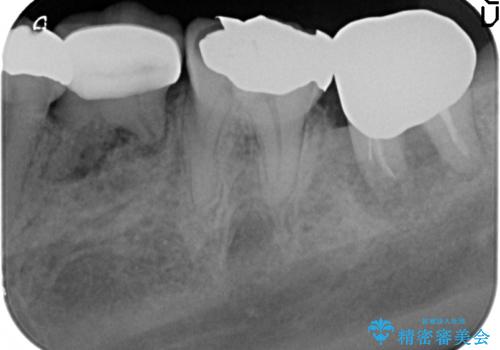

最後方臼歯周囲には大きな透過像が見られ、破折が強く疑われること抜歯が想定されることを理解していただき銀歯を除去したところ破折が認められたため抜歯を行いました。

良好なインプラントの植立を行うためには、十分な骨量があることが必須条件です。

術前、歯の破折により大きな骨の吸収が認められていたため骨量を十分に回復するために抜歯と同時に歯槽堤保存術を行い十分な骨量の回復をすることができました。